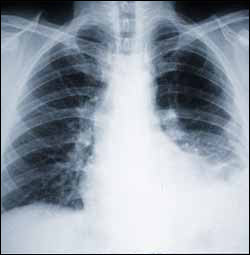

Asbestos is toxic. The inhalation of asbestos fibers can cause serious illnesses, including malignant mesothelioma, lung cancer, and asbestosis (also called pneumoconiosis). Since the mid 1980s, many uses of asbestos have been banned in several countries.

When asbestos-containing materials are disturbed the fibers are released into the air, where they can lead to deadly diseases such as mesothelioma.

Signs and symptoms of mesothelioma include shortness of breath due to pleural effusion (fluid between the lung and the chest wall), chest wall pain, and constitutional signs such as unexplained weight loss. The diagnosis may be suspected based on chest X-ray and CT scan findings, but must be confirmed either by examining serous effusion cytology or with a biopsy (removing a sample of the suspicious tissue). A thoracoscopy (inserting a tube with a camera into the chest) can be used to acquire biopsy material, and allows the introduction of substances such as talc to obliterate the pleural space (a procedure called pleurodesis), preventing more fluid from accumulating and pressing on the lung. Despite treatment with chemotherapy, radiation therapy or sometimes surgery, mesothelioma carries a poor prognosis. Research about screening tests for the early detection of mesothelioma is ongoing.